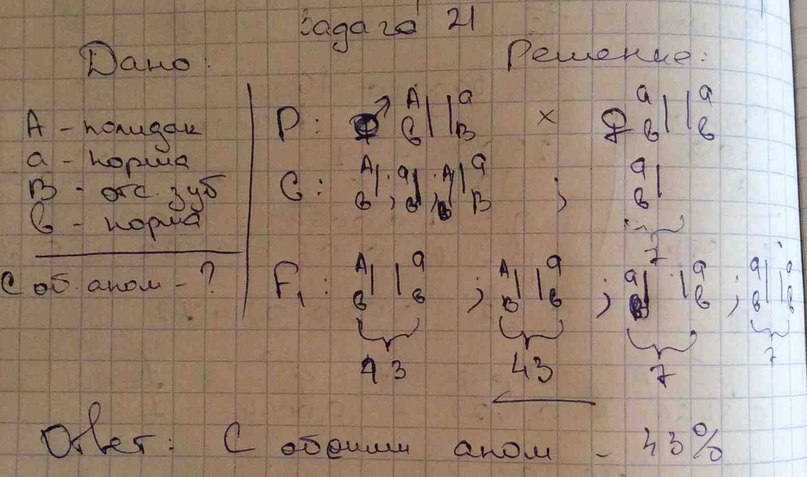

Генетика гемофилии: рецессивные гены и их проявления